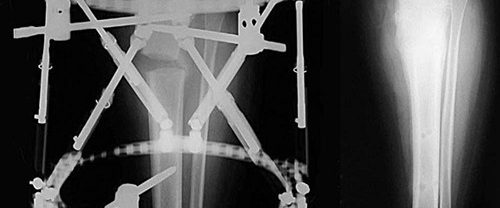

İlizarov Yöntemi Nedir? İlizarov yöntemi, Sovyet Ortopedik Cerrah Profesör Gavriil Ilizarov tarafından geliştirilmiş bir cerrahi tekniktir. Bu yöntem, kemiklerin iyileşmesini teşvik etmek ve deformiteleri düzeltmek için kullanılan bir dizi prensibe dayanır. İlizarov yöntemi, kemikleri doğrudan manipüle etmek yerine, kemiklerin etrafına dıştan bir cihaz (fiksatör) yardımıyla bir çerçeve oluşturarak çalışır. Bu çerçeve, kemiklerin doğru pozisyonda iyileşmesini…